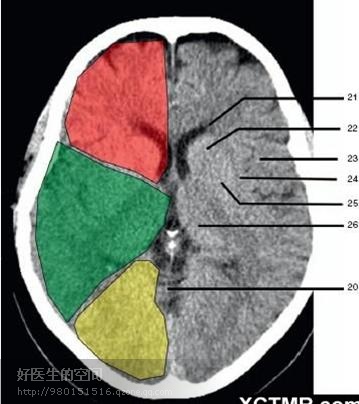

22、尾状核头部 (Head of caudate nucleus) 23、岛叶 (Insular cortex) 24、外囊 (External capsule) 25、豆状核(Lentiform nucleus) 26、丘脑(Thalamus) 绿色部分为颞叶(Temporal Lobe),浅红色部分为额叶(Frontal Lobe),黄色部分为枕叶(Occipital Lobe)